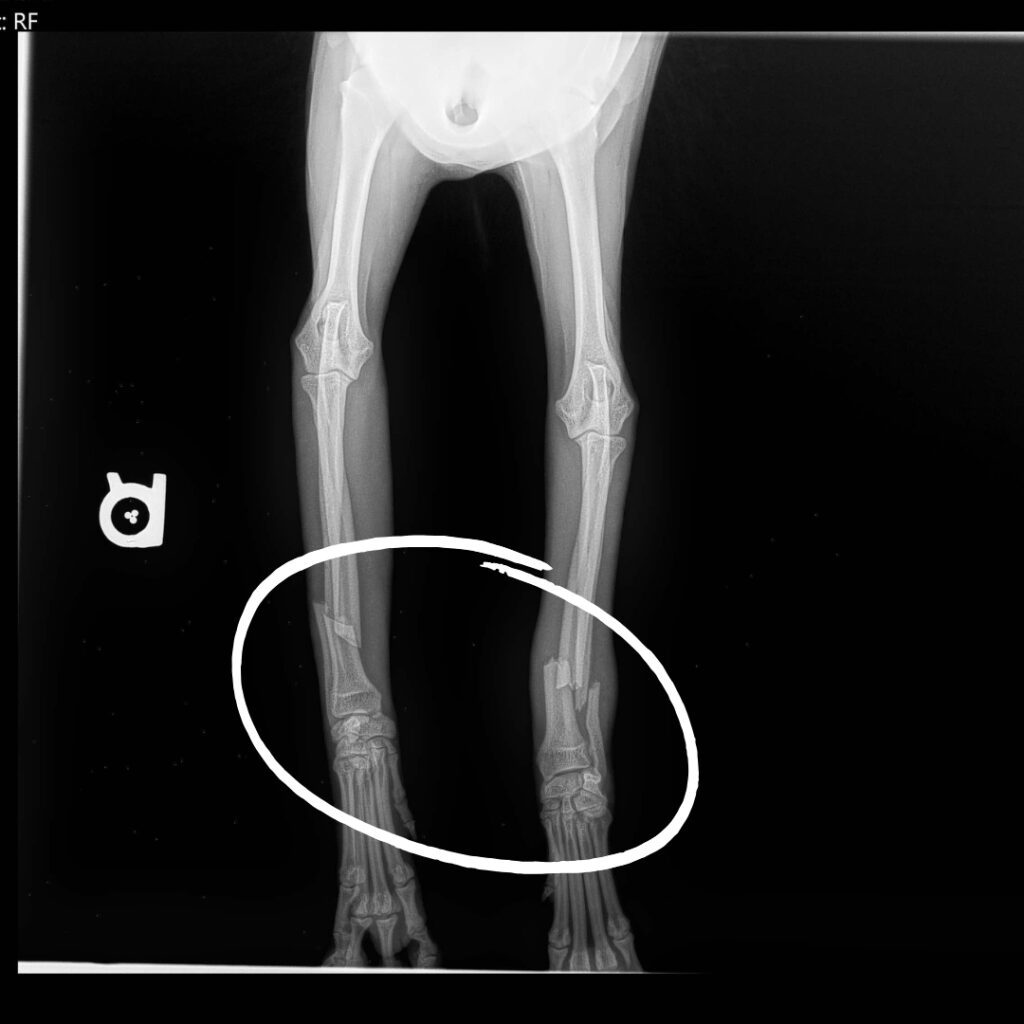

Riga Tony recently arrived at our Sam Swope Pet Treatment and Lifesaving Center in desperate need of our help after being hit by a car. He was clearly injured and unable to bear weight on either of his front legs without whining in pain. Our hearts broke for this poor two-year-old pup, so we welcomed him with open arms and promised to help as best as we can. We provided Riga Tony with medication to help him find relief and keep any potential infections from setting in, before taking several x-rays. Our worst fears were quickly confirmed: both of Riga Tony’s front legs are broken in two places.

Riga Tony’s recovery won’t be quick or easy. We’ve splinted his injuries, and have called a specialist who will soon determine if they can help this sweet pup make a full recovery without needing an amputation. Amputation surgery may still be necessary in the future, but our hope is that he will be able to keep at least one of his front legs when all is said and done. For now, Riga Tony is resting under our vet team’s watchful eyes. We will keep you posted on his progress but in the meantime, please donate to support lifesaving medical care for vulnerable animals just like Riga Tony.